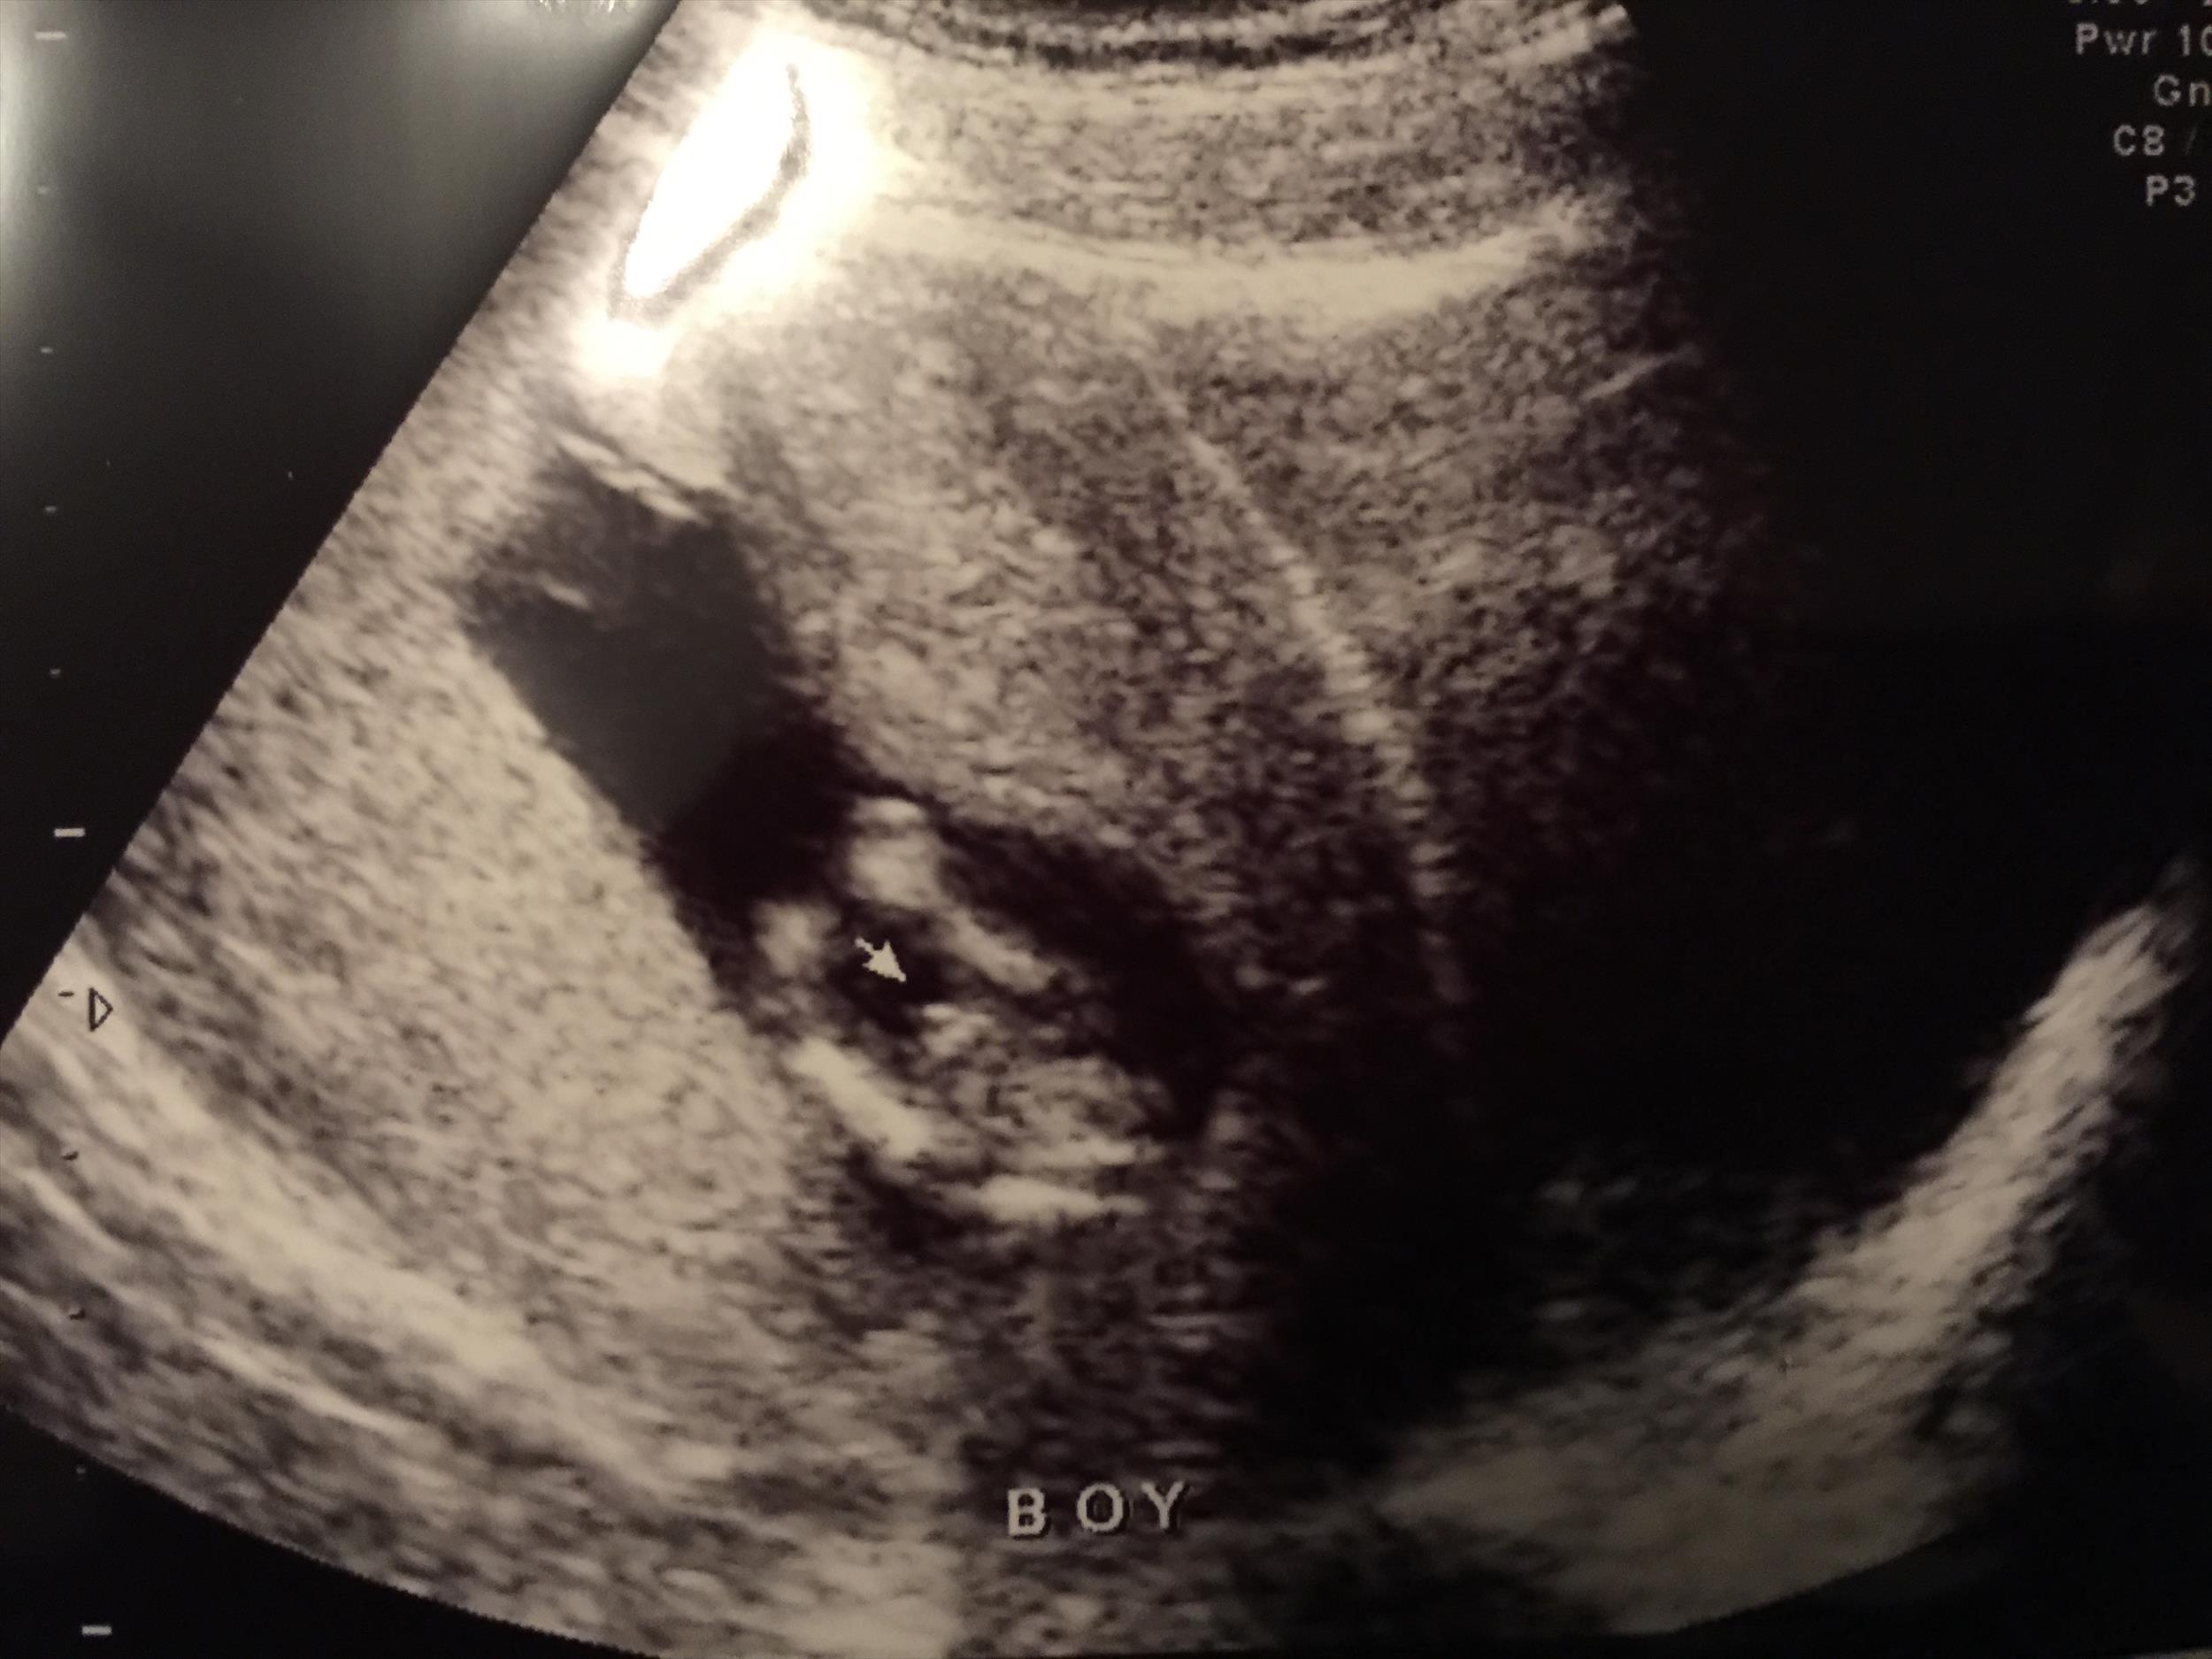

Just got a gender ultrasound at 13wk5d. Sonographer says "boy" but I wanted to make sure she didn't make a mistake. Please let me know if it's pretty obvious in these pictures. Thanks so much :)